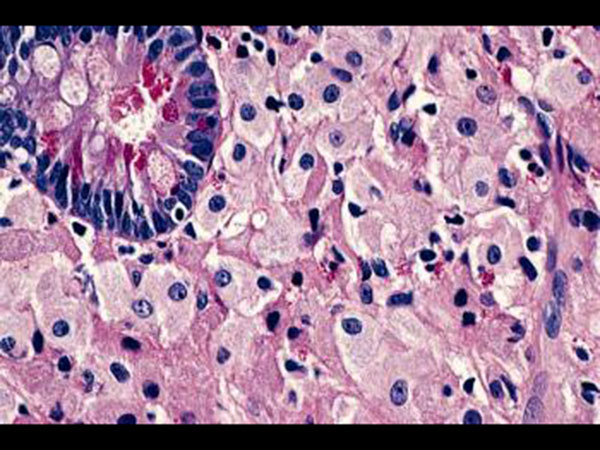

In some cases, a biopsy might be conducted to reach a conclusive decision about the diagnosis of Whipple disease. A tissue sample is collected from the lining of the small intestine [11] . The tissue is examined under a microscope for the presence of disease-causing bacteria and their lesions.